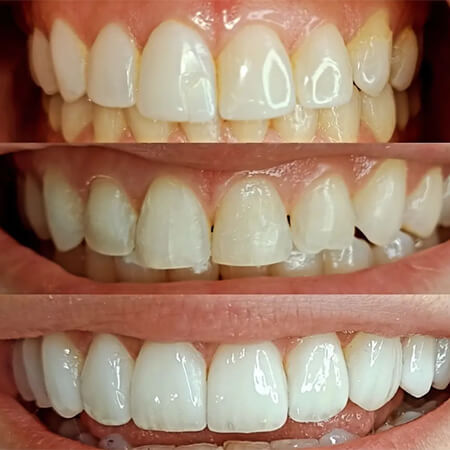

Before and After Gallery